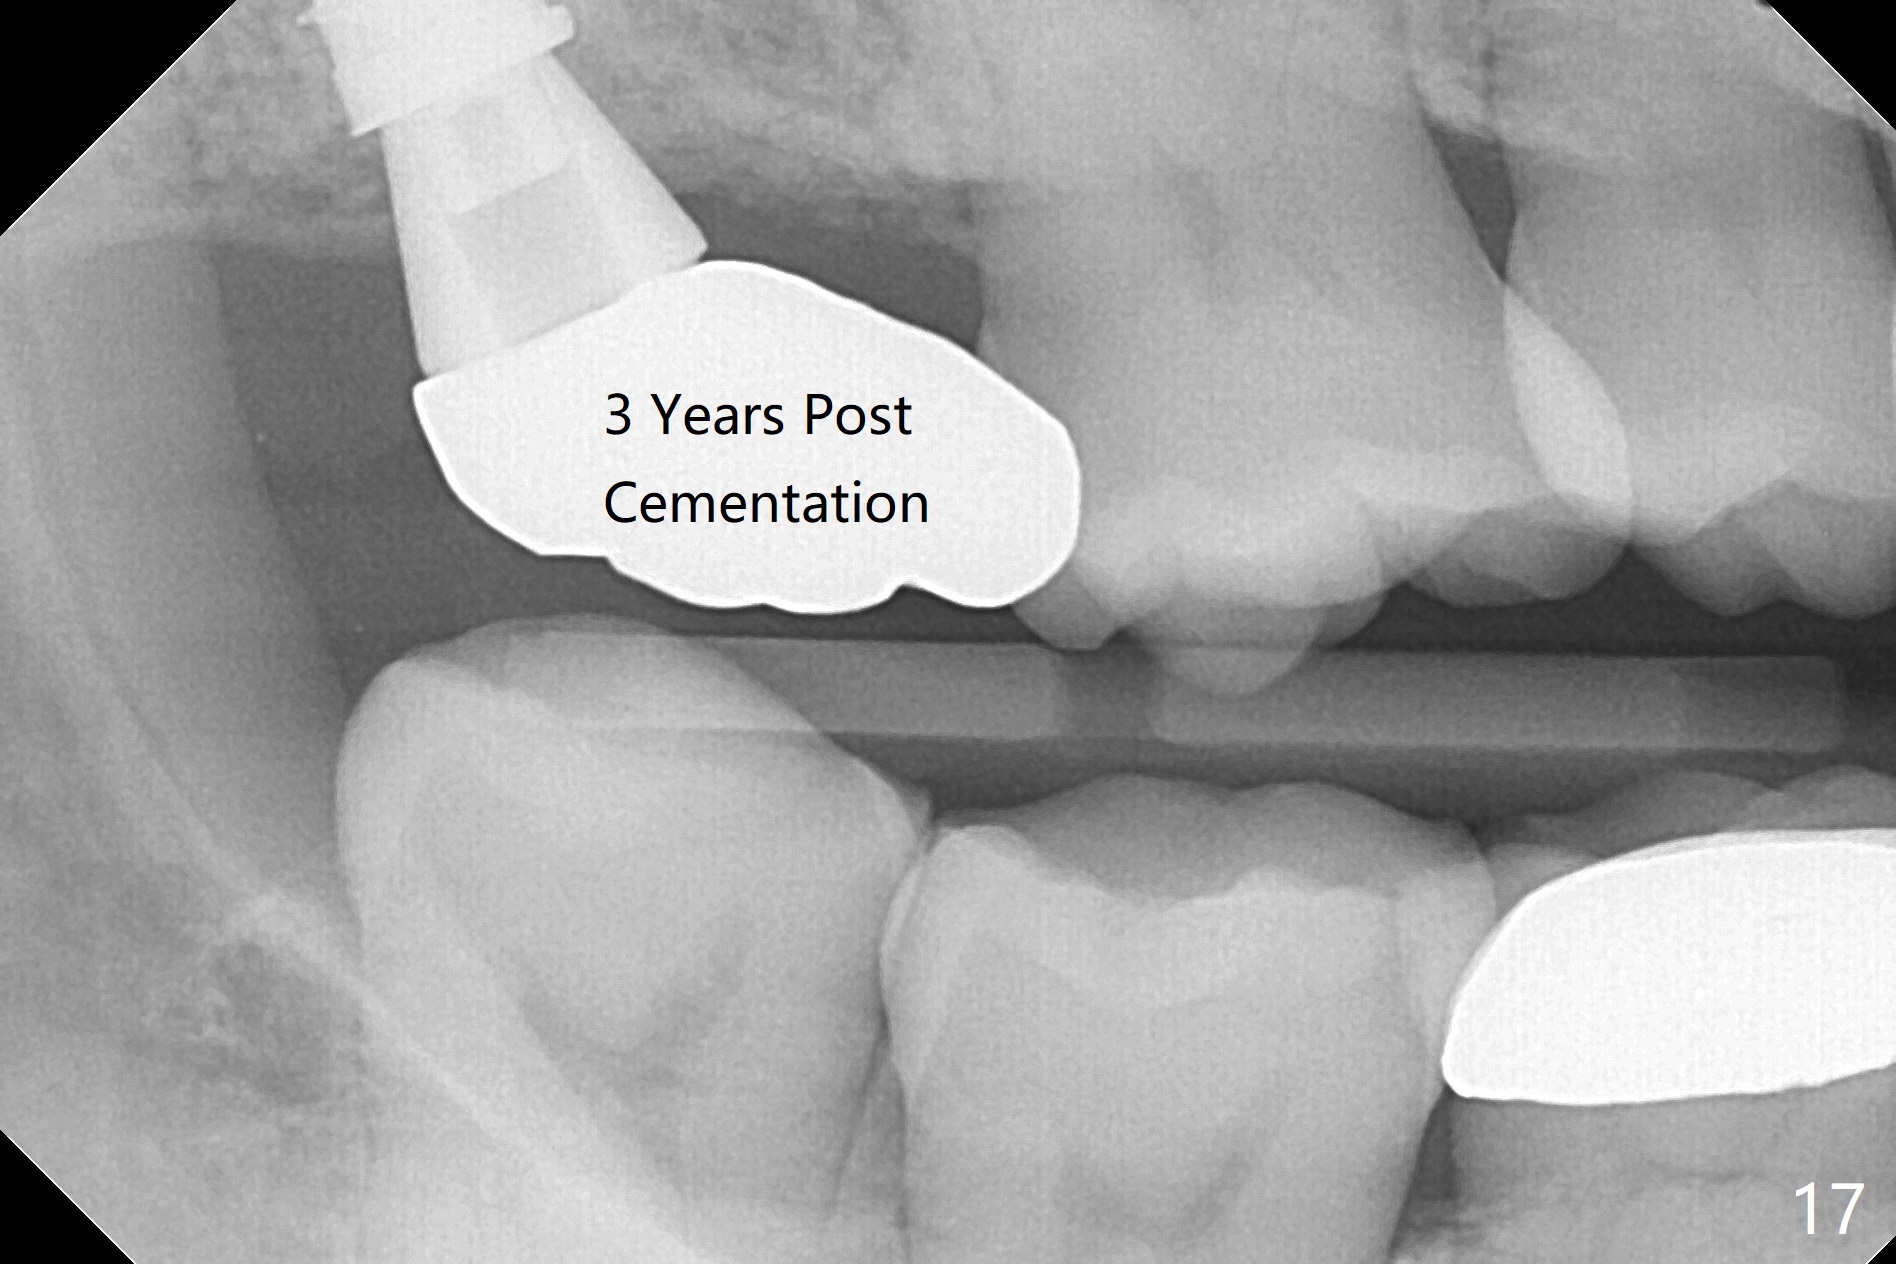

Fig.5 shows the mesial slope of the socket (M), which is more or less the center of the socket mesiodistally. If the osteotomy were set up in the red circle (Fig.6) in the mesial slope (Fig.8 green dashed line), the trajectory of 4.5x11 mm dummy implant (Fig.7) would be more ideal (Fig.8 red outline) with more native bone contact. Finally a longer IBS implant is placed (4.5x15 mm, Fig.9,10) to achieve primary stability (50 Ncm). When the provisional is removed for impression 3 months 10 days postop, the implant is found to have been placed distopalatally (Fig.13), which should have been avoided. It appears essential to use guide for a distal implant. It is agonizing to re-encounter the off-axial implant (Fig.14) and the distopalatal access hole (Fig.15) 1 year post cementation. It is also amazing that the abutment screw has not loosened. A fair-sized piece of bone graft has just been removed buccally (Fig.15,16). The patient complains of sensitivity 2 years 3 months post cementation, although there is no abnormality around the implant crown. Guided surgery is essential to avoid restoration complication. There is no thread exposure nearly 3 years post cementation; in fact the apical portion of the abutment is covered by the bone (Fig.17,18).